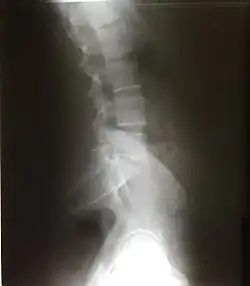

Есть 2 вида изгиба позвоночника: лордоз и кифоз. Лордоз — это те части позвоночника, которые выгнуты вентрально (вперед) — шейный и поясничный. Кифоз — это те части позвоночника, которые выгнуты дорсально (назад) — грудной и крестцовый.

Поясничный отдел

В поясничном отделе располагается 5 позвонков. На поясничный отдел приходится очень большая масса, поэтому тела поясничных позвонков самые крупные. Остистые отростки направлены прямо назад. Суставные отростки обращены сагиттально. Есть рёберные отростки (рудименты рёбер), добавочные отростки (остатки поперечных отростков, не слившиеся с ребром), сосцевидные отростки — след прикрепления мышц.